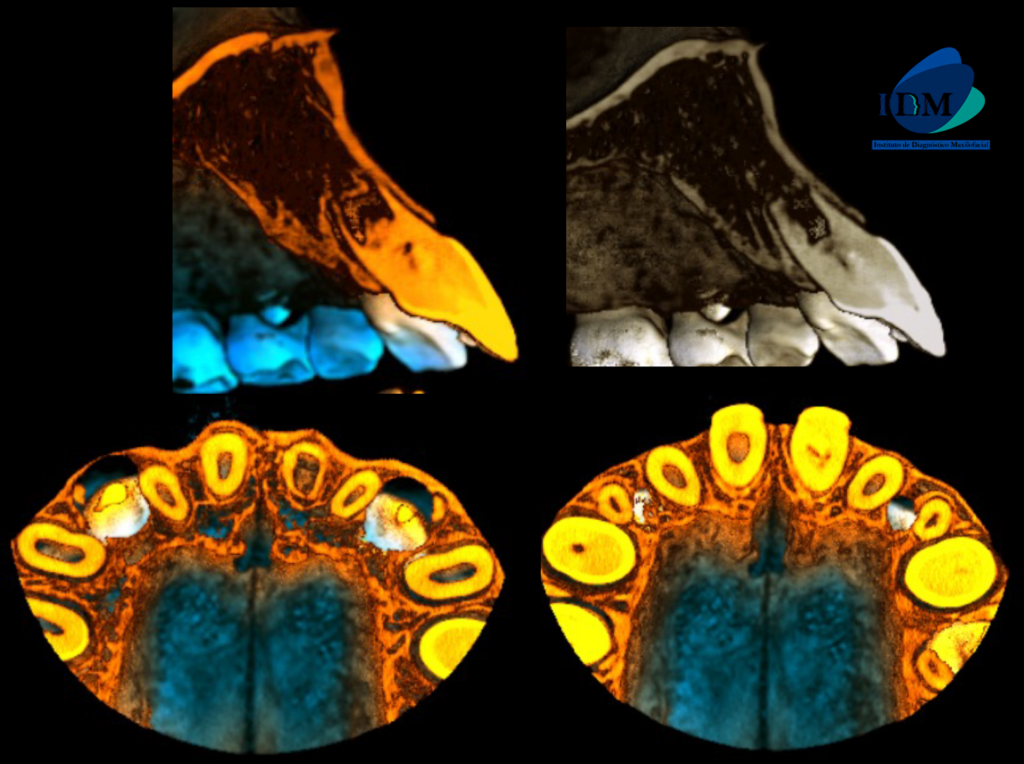

En la reconstrucción 3D se representa la obliteración del conducto y foramen apical amplio de la pieza 21 (Figura 4)

RECONSTRUCCIÓN 3D